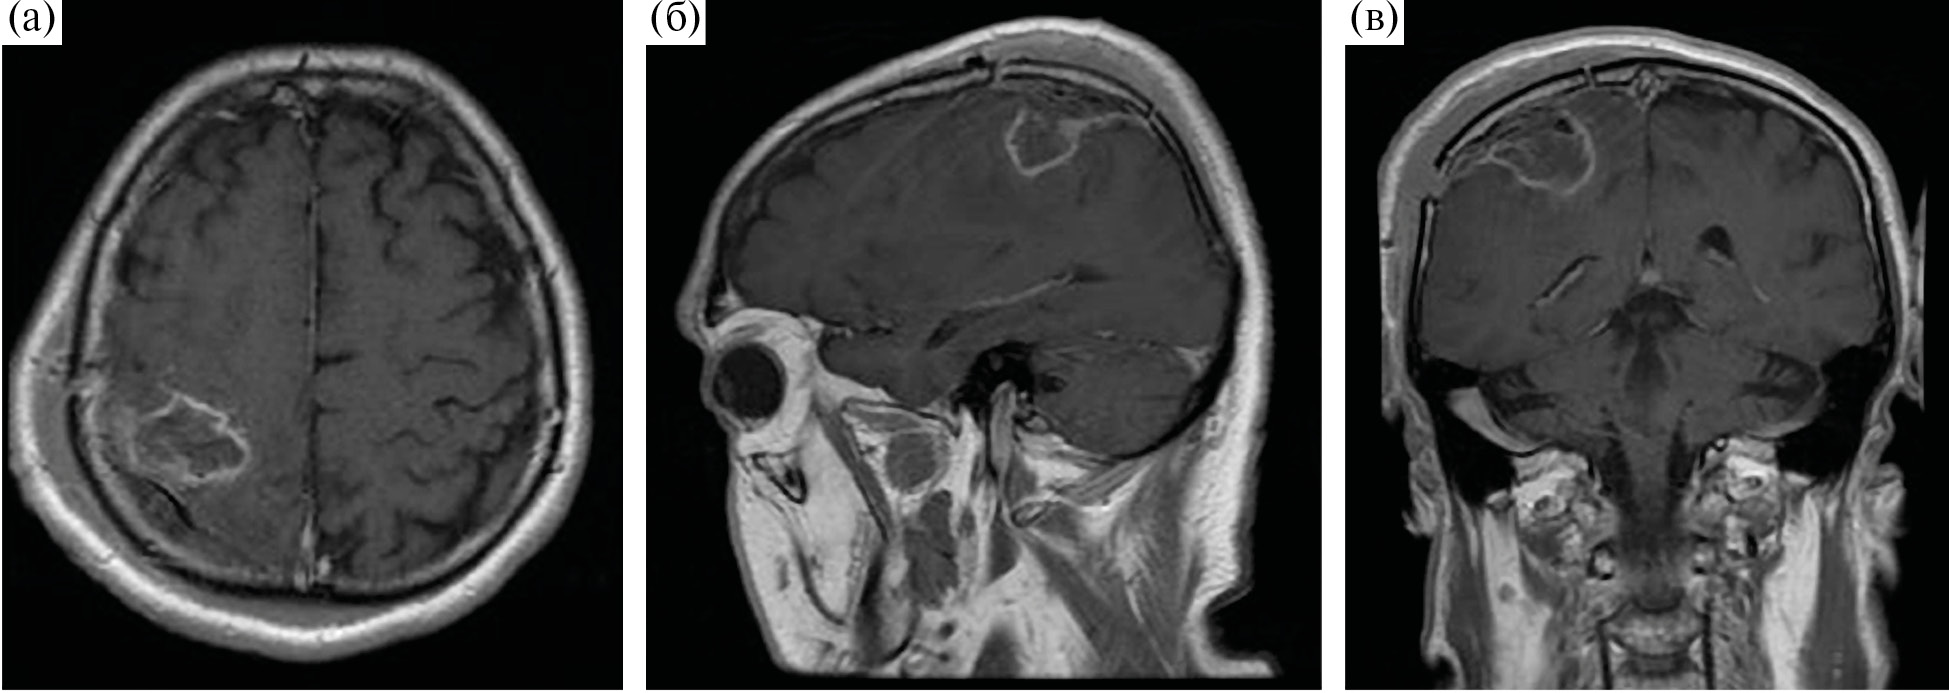

Пациент М., 59 лет, госпитализирован в НМИЦ нейрохирургии им. академика Н. Н. Бурденко с жалобами на слабость, неловкость и онемение в левых конечностях. Данные жалобы возникли около 2 месяцев назад и постепенно нарастали, что послужило поводом для выполнения МРТ головного мозга с в/в контрастированием, которая выявила объемное образование правой теменной доли с умеренным перифокальным отеком, предположительно глиома высокой степени злокачественности, прилежащая к функционально значимым двигательным зонам коры мозга и пирамидного тракта (рис. 3).

Рис. 3. МРТ до операции. Внутримозговая опухоль правой теменной доли, прилегающая к прецентральной извилине. Опухоль кольцевидно накапливает контрастный препарат и окружена небольшой зоной отека-инфильтрации. (а) – аксиальная проекция, Т2-FLAIR, (б) – аксиальная проекция, Т1 + С, (в) – сагиттальная проекция, Т1 + С; (г) – фронтальная проекция, Т1 + С.

Fig. 3. Preoperative MR-images.

При неврологическом осмотре на момент госпитализации у пациента отмечались гипестезия и снижение мышечной силы в левых конечностях до 4 баллов.

Учитывая локализацию процесса и клиническую картину заболевания, в качестве предоперационной подготовки пациенту были проведены фМРТ с визуализацией моторных зон и МР-трактография с построением КСТ (рис. 4).